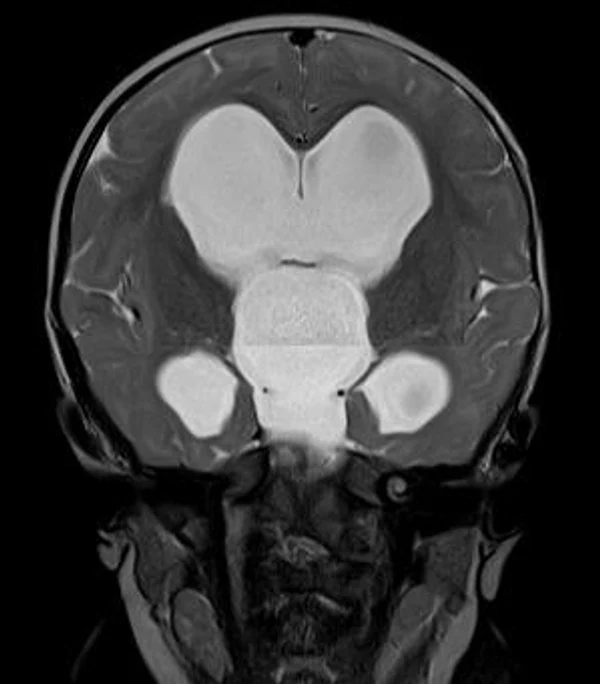

кисты, аномалии Денди-Уокера и др.Операции при внутричерепных кистах. В основном встречаются арахноидальные кисты различных локализаций и кисты сосудистых сплетений боковых желудочков. Пациентам с врождёнными кистами операции проводятся в следующих ситуациях: увеличении объема кисты в динамике, наличии клинических проявлений, компрессии и дислокации мозговых структур, наличии окклюзии ликворных путей. Нами используются 2 способа хирургического лечения кист: эндоскопическая перфорация стенок кист и открытая резекция кист. Открытая резекция кист проводится при ретроцеребеллярных арахноидальных кистах (рис. 2), при арахноидальных кистах межполушарной щели при отсутствии непосредственного контакта их стенок со стенками расширенных желудочков головного мозга и повторного увеличения кист средней черепной ямки после эндоскопической кисто-цистерностомии. Техника операции заключается в проведение краниотомии и максимальном иссечении стенок кист с созданием широкого сообщения кист с субарахноидальным пространством. Эндоскопические операции проводятся при арахноидальных кистах межножковой и пинеальной цистерн, арахноидальных кистах межполушарной щели при тесном контакте их стенок со стенками расширенной желудочковой системы (рис. 3), первично при арахноидальных кистах средней черепной ямки, а также при кистах сосудистых сплетений боковых желудочков. При арахноидальных кистах межножковой цистерны эндоскопически проводится перфорация стенок кисты, сообщая ее с просветом III желудочка и межножковой цистерной – эндоскопическая вентрикуло-кисто-цистерностомия (рис. 4). При арахноидальных кистах пинеальной цистерны проводится перфорация кисты в передне-верхних её отделах с созданием сообщения полости кисты с просветом III желудочка – эндоскопическая кисто-вентрикулостомия. С целью предотвращения облитерации сформированного отверстия иногда в полость кисты под контролем эндоскопа вводится стент перфорированный на протяжении (рис. 5, 6). Эндоскопическая кисто-цистерностомия выполняется при арахноидальных кистах средней черепной ямки. При этом создается широкое сообщение кисты с базальными цистернами. При кистах сосудистых сплетений боковых желудочков проводится их вскрытие в просвет боковых желудочков – эндоскопическая кисто-вентрикулостомия. При множественных кистах проводится их хирургическое сообщение между собой – интеркистосмия